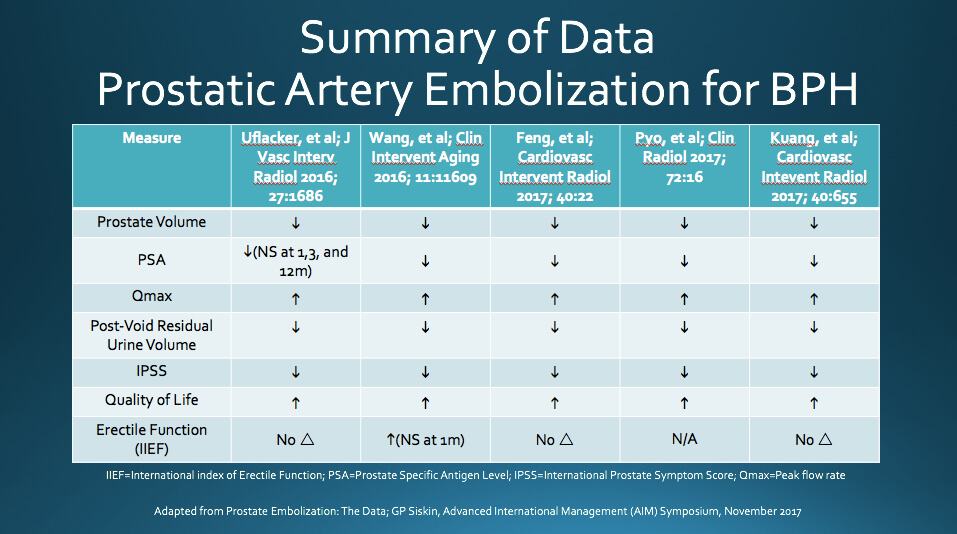

PAE has been shown to reduce patient’s International Prostate Symptom Score (IPSS) and improve quality of life (QOL). The IPSS is a scoring system used to screen for and diagnose BPH, monitor symptoms, and guide management decisions. A study performed by Carnevale et al. demonstrated PAE clinical success rate of 91% and a found significant sustained improvement in IPSS following PAE [2]. Similarly, Pisco et. al studied 255 patients diagnosed with BPH and moderate to severe lower urinary tract symptoms who underwent PAE and found clinical success rates of 82%, 75%, 72%, and 72% at 1, 12, 24, and 26 months, respectively [3]. A recent meta-analysis of PAE for BPH, which included the aforementioned studies, found an overall decrease in IPSS of 13%, 15%, and 20% at 1, 6, and 12 months after treatment, respectively. The meta-analysis also found a sustained improvement in QOL following PAE [4]. See below for a summary of data from additional recent PAE studies.